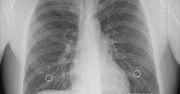

W Polsce co 20 minut ktoś umiera na raka płuca. Szybka diagnostyka i leczenie mogłyby poprawić te statystyki